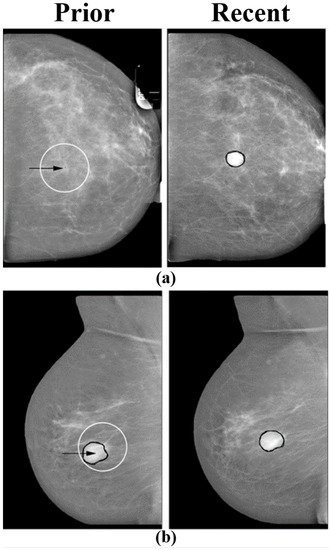

6. Temporal Subtraction